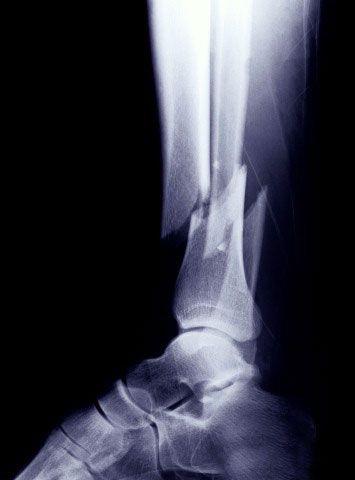

Abiertas: son cuando los extremos del hueso roto salen al exterior, destruyendo la piel y/o los músculos, presentándonos una herida.

Cerradas: son cuando se rompe un hueso sin salir al exterior.

Subtipos de fracturas

Tallo verde: en este caso el hueso no se rompe, pero se deforma (esto ocurre en los infantes)

Por impacto: el hueso se incrusta dentro de sí mismo, acortando su tamaño.

Conminuta: es cuando parte del hueso es destruido por un gran peso que pasa sobre él.

Fisura: cuando el hueso se agrieta, pero no se rompe.